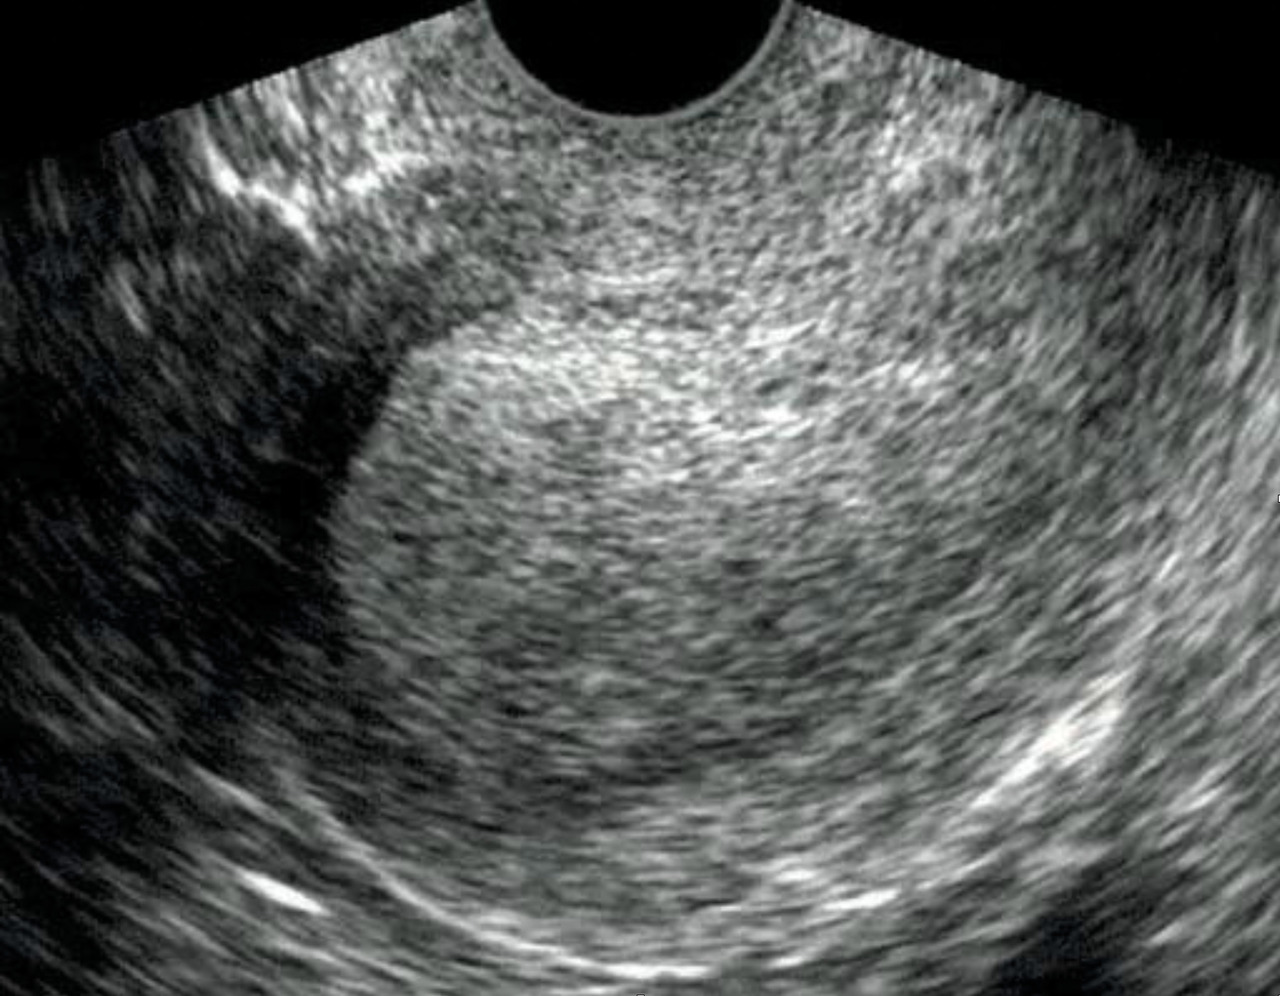

Une échographie pelvienne est réalisée pour confirmer le diagnostic clinique et pour apprécier le volume utérin qui peut avoir des contours déformés par les léiomyomes. Les fibromes ont un aspect échographique caractéristique, arrondi, légèrement hypo­échogène par rapport au myomètre, avec vascularisation périphérique (fig. 5). L’échographie permet la cartographie des fibromes ainsi que le suivi de leur évolution.